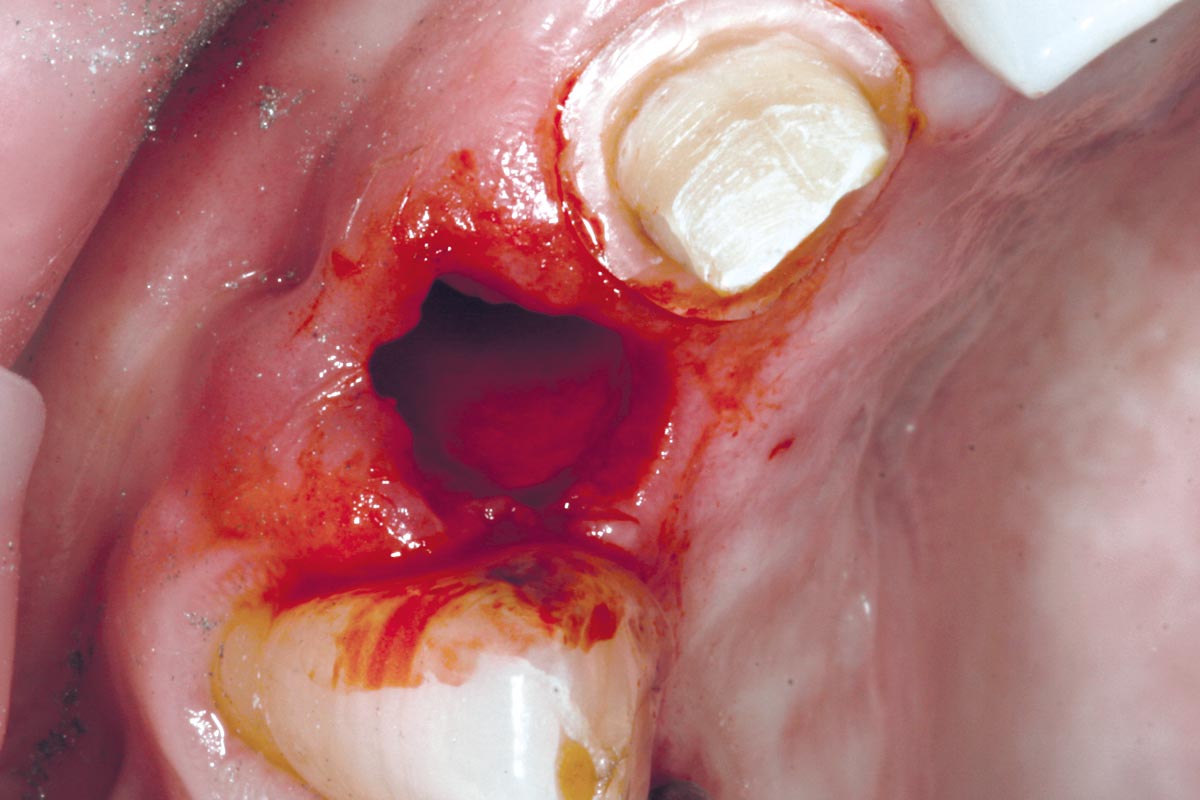

4/19 - Site after extractionBone augementation with maxresorb® - Dr. R. Cutts